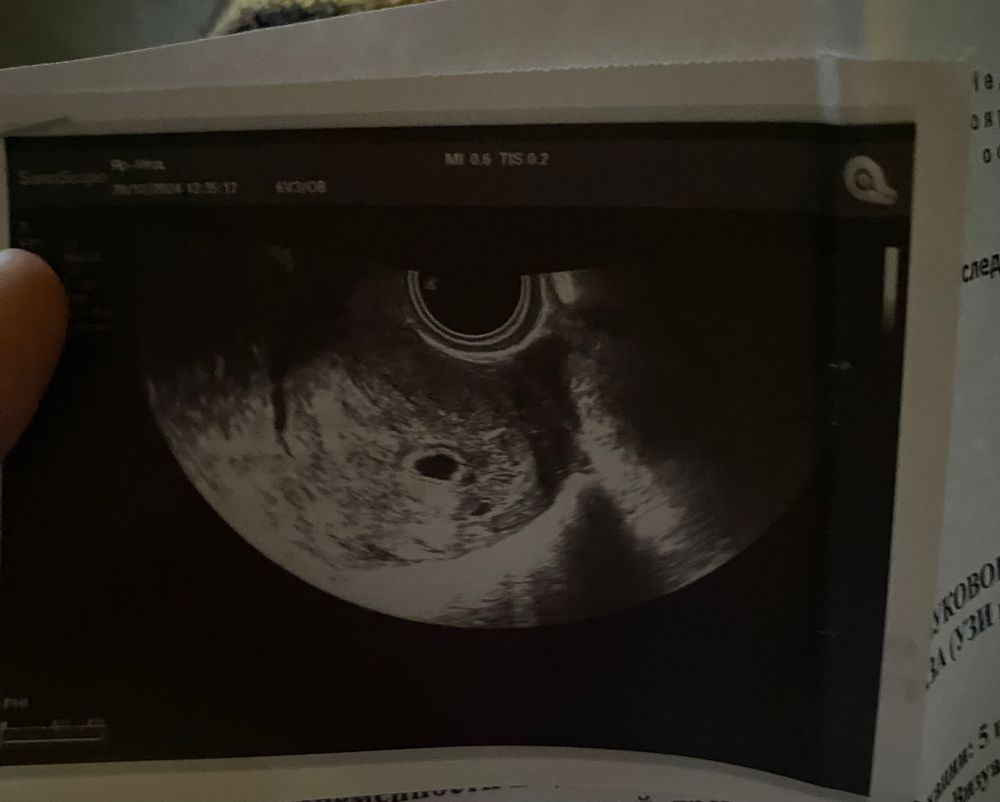

Девочки,сходила на узи и только потом заметила,что рядом с плодным яйцом есть 2 пятнышка,что это может быть?Двойни же не может быть?)

Двойня иначе выглядит. Инфа 100% 😁

Думаю узист бы вам сразу сообщил, ну или написал в справке.. им виднее, кто там мальчик или девочка, один или двойня.. лучше у них это спрашивать.. по картинке с одного кадра может быть всё что угодно..